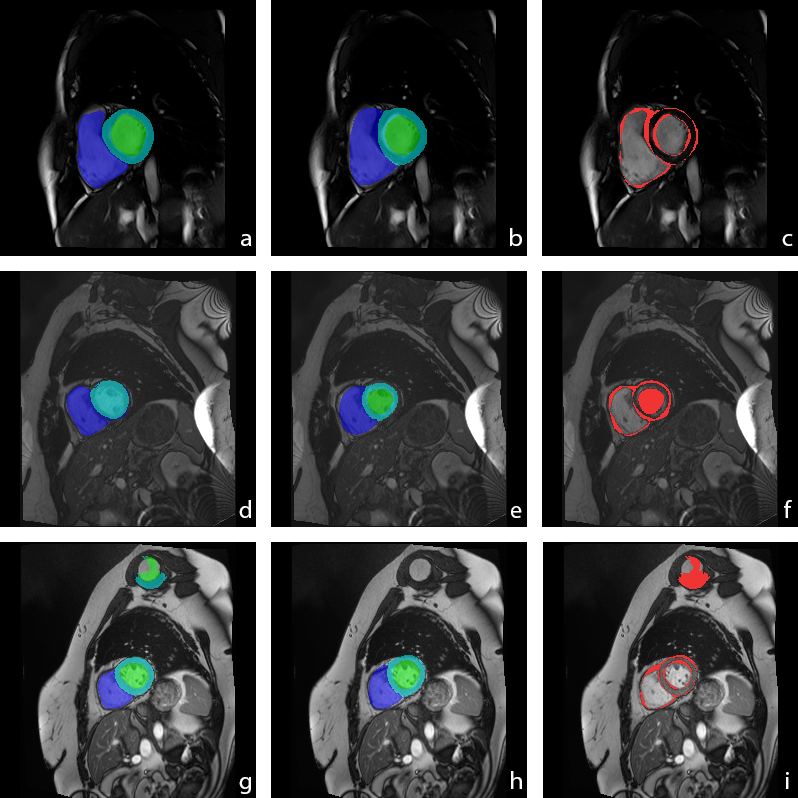

Through the use of alert flags we were able to detect 16 cases for which the challenge platform had reported NaN values indicating errors in the submitted results. Fifteen cases were flagged as erroneous () and one as suspicious () by our framework. Fig. 4 middle and bottom row illustrates two of these cases. The middle row presents a segmentation flagged as erroneous, where the inconsistency map confirms that the left ventricle has not been segmented. The bottom row shows the case of a segmentation flagged as suspicious, where the left ventricle’s pHD is high (), although the is within normal range. The inconsistency map confirms the clear segmentation error.

Additionally, Fig. 4 top row illustrates an example of a segmentation mask that has not been flagged, i.e. a segmentation result considered good by the -type metrics of our framework ( and for all LV, RV and MYO). The inconsistency map (Fig. 4c) flags pixels in the edges of all the structures as suspicious. While it is clear from the images that the segmentation mask for the RV (, ) has some errors in the edges, which require a revision, the flagged pixels in the LV and MYO are more difficult to assess. In such a case, a more informative -type measure than the selected XOR is desirable.